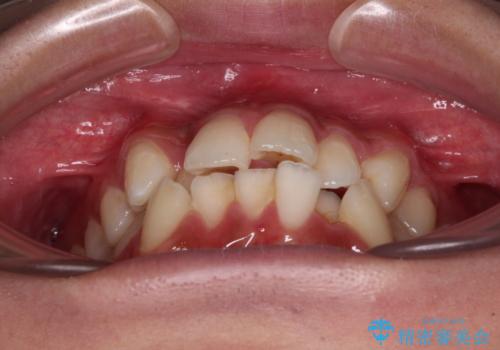

- 八重歯と口元の閉じにくさを気にして来院された患者様です。

非抜歯矯正で歯列を整えると、治療後に口元が今よりも突出する可能性が高かったため、上下左右の第一小臼歯4本を抜歯し、ワイヤー装置にて矯正治療を行うこととしました。